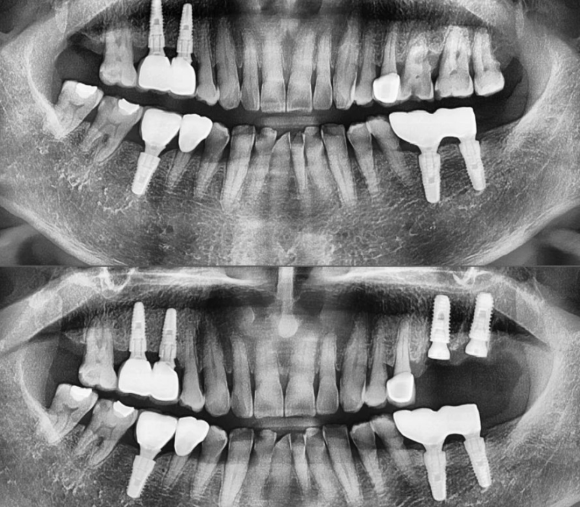

2022.4.2 상발즉임 (상담후발치후즉시임플란트)

중격을 이용, 미끌림 방지위해 라운드버 홈 형성 후 드릴링.

수술시간 7분

저희 숭실대 입구역 리더스진 치과는 한달 평균 임플란트 60~100개를 꼼수 없이 가장 좋은 재료와 기술로 원칙적으로 식립하는 치과입니다.